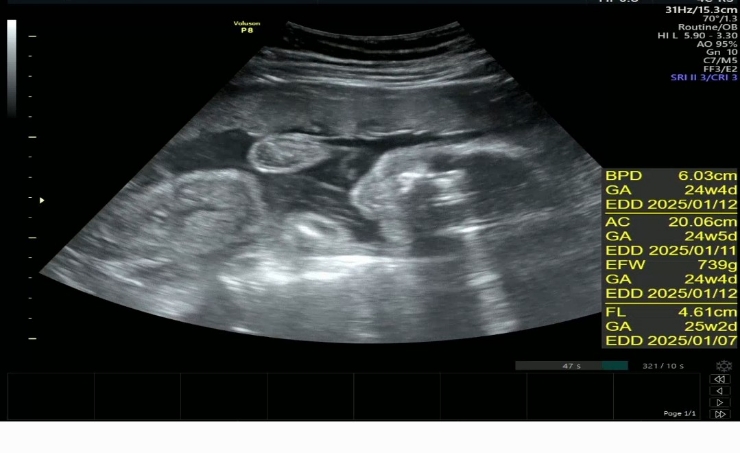

30w 0d 정기검진

2024.12.19

어느덧 30주라네 8개월중반 애기가 뱃속에서도 딸꾹질을 엄청하는데 초음파보는데도 하고있어서 딸꾹질하는...